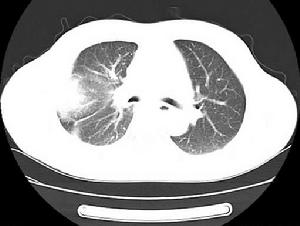

2.肺癌肺癌早期可出現四肢關節疼痛。肺癌侵及胸膜可引起胸痛,骨轉移引起骨痛,顱腦轉移引起頭痛,肺尖部癌瘤侵及或壓迫臂叢神經或交感神經。可出現嚴重的肩、臂痛和Horner綜合徵。

(1)組織毀壞:當腫瘤侵及胸膜、腹膜或神經,侵及骨膜或骨髓腔使其壓力增高甚至發生病理性骨折時,病人可出現疼痛,如骨轉移、骨腫瘤所致的骨痛。肺癌侵及胸膜可致胸痛。肺尖部腫瘤侵及臂叢可出現肩臂疼痛等。